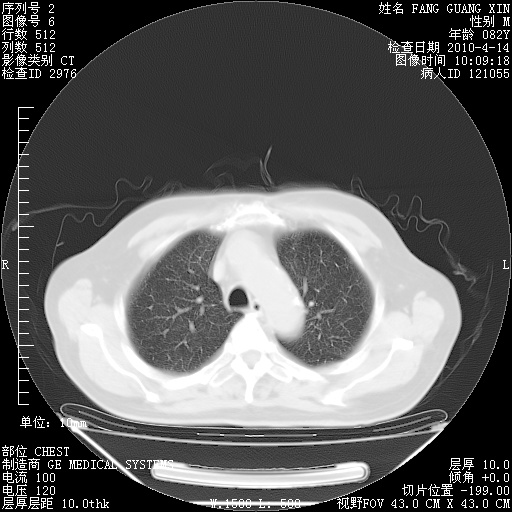

肺部CT平扫未见异常。

4月14日肺部CT